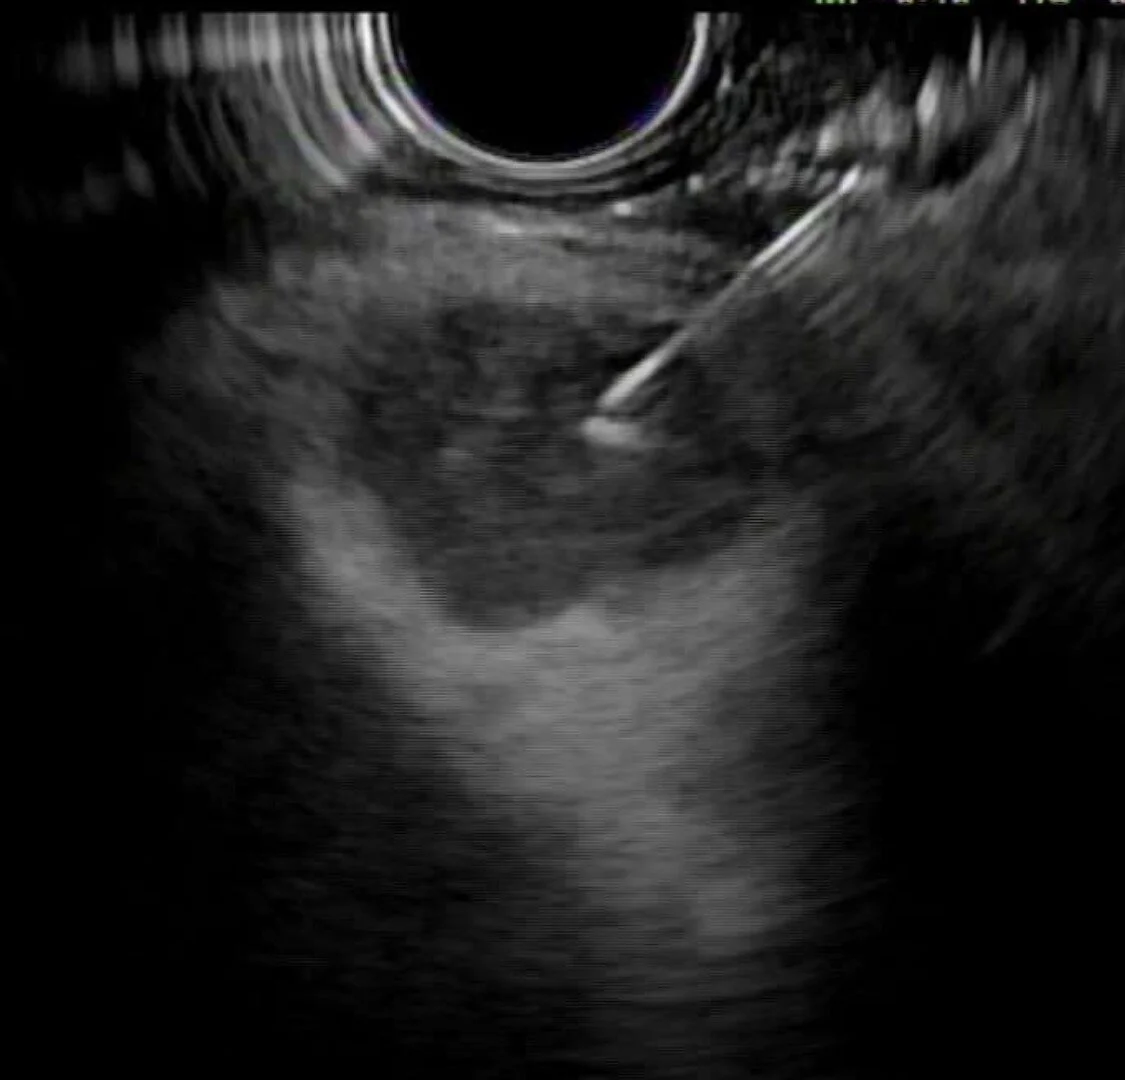

Image captured from EUS FNA. They nailed it!